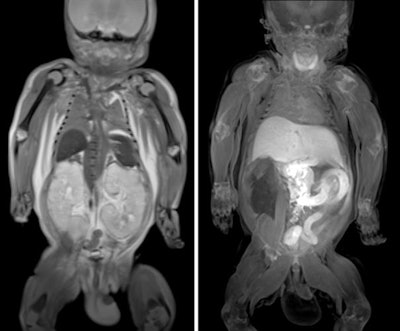

The main indications to use imaging are when parents don't want an invasive autopsy, but we can offer imaging for all kinds of perinatal and neonatal deaths, including miscarriages, stillbirths, and confirming congenital abnormalities following termination of pregnancy. We try to use the right imaging for the right indication. For example, if we have a baby whom we think may have died from skeletal dysplasia, an x-ray might give us all the answers that we need to then proceed to genetic testing. In congenital heart disease and intracranial abnormalities, it is much more appropriate to use postmortem MRI, while in cases of rib fractures in suspected physical abuse, it is best to use CT.

In postmortem imaging, quite a lot of findings will be normal, but that can still be reassuring for parents who want to know whether or not, for example, there may have been a problem with the child or with the baby or with the placenta, or whether it was just something that happened in pregnancy. Doing a whole-body MRI of the baby after it has died and showing parents that everything is normal can be quite reassuring.

Otherwise, we need to look out for common congenital abnormalities, where the heart, brain, or kidneys, for example, haven't developed properly and have probably contributed to the death. In older children, we often pick up on infections as the cause of death, and some have died from a known cancer and we're able to identify the extent of those.